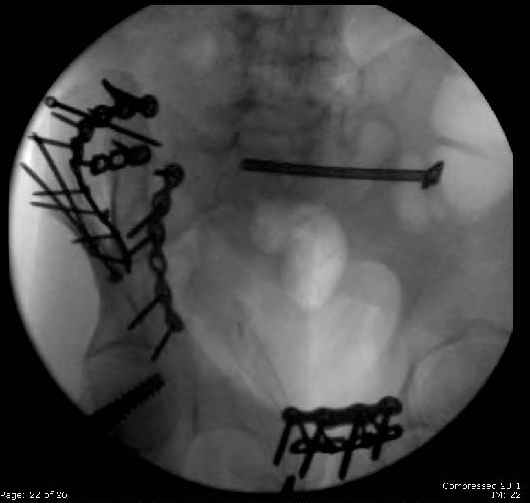

Here are the postop fluoros.

First exposed symphysis & clamped w/Faraboeuf as close to anatomic as possible.

Then extended to R ilioinguinal,really just the lateral window.

Reduced the triangular wedge piece of iliac wing to posterior intact ilium (crescent), held w/k-wire, then used 3-hole push plate to keep from moving, lagged from lat-med w 3.5 screw.

Then 6-hole plate along brim with 1 screw in R sacral ala. Then lagged 2 screws along crest A --> P. finally 10-hole plate along inner aspect of crest. R posterior ilium still a bit stepped off.

Symphysis then 'fine-tuned' & reduced as close as possible to anatomic (but, still with forward rotation of R hemipelvis - or, is it extension?) Accepted that amount of deformity and plated symph

with 4-hole symphyseal plate.

Fluoroed L SI joint and it seemed stable, but wide. So, applied c-clamp to try to squeeze down L SI joint (and note, on the last slide attached, that it's still wide), and got it closer. Single perc Iliosacral screw 40mm thread.

Applied second plate anteriorly on symphysis as I wasn't confident L SI was as stable as it could be and wanted to protect it better.